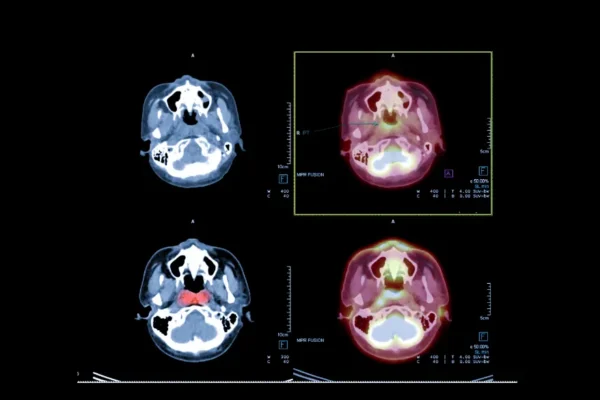

- PET CT